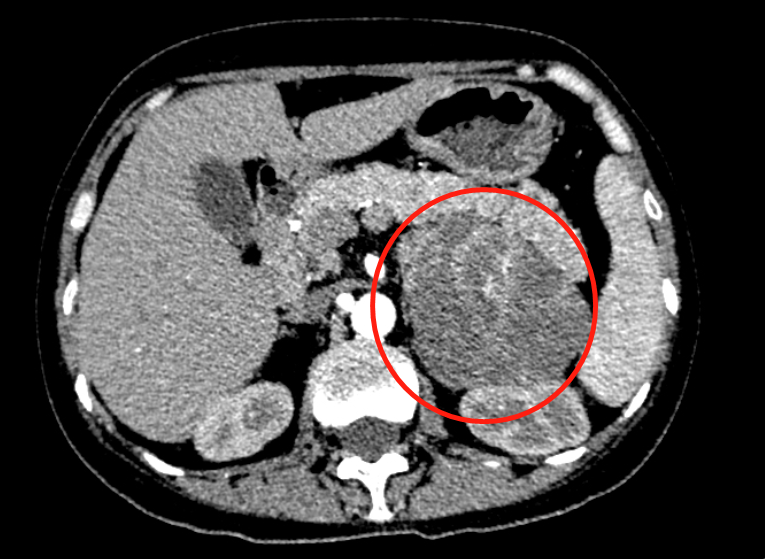

团队详细进行内分泌激素检测和功能试验,开展定性、定位检查,发现招姨存在典型的低血钾、高尿钾排泄、碱中毒、皮质醇显著增多,大小地塞米松功能试验均不被抑制。抽丝剥茧地查找病因,沈洁院长团队终于找到在左侧肾上腺长了 7 cm 的巨大肿块。

也正因为该肿块,造成了招姨的皮质激素异常分泌,进而导致顽固性低钾血症,并且该肿块 1 周内快速生长至 9 cm。